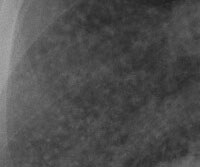

Røntgenbilde av en frisk lunge

Lunge uten silikose